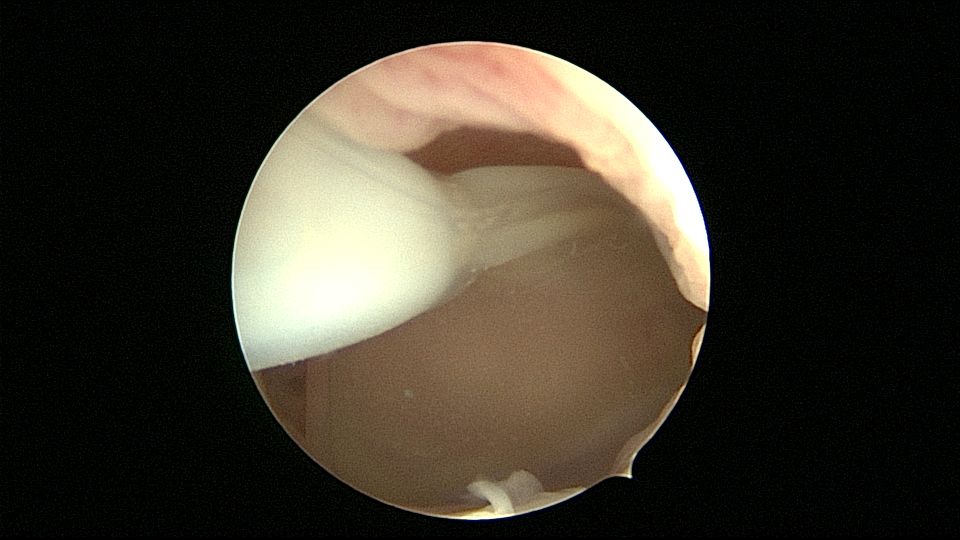

患者35岁,G5P0,继发不孕10年,10年前外院开腹宫外孕手术1次,试管失败1次。外院B超提示宫腔粘连,2021年4月在成都西囡妇科医院做宫腔镜检查,发现宫腔粘连。2021年11月到我院做宫腔镜分粘手术,术中见宫腔两侧及右侧宫角致密粘连,内膜片状充血,单极电切分粘,恢复宫腔形态,显露双侧输卵管开口。2021年12月宫腔镜二探取球囊,宫腔形态正常,双侧输卵管开口可见。分粘后再次试管成功,足月分娩。现40岁,G6P1。